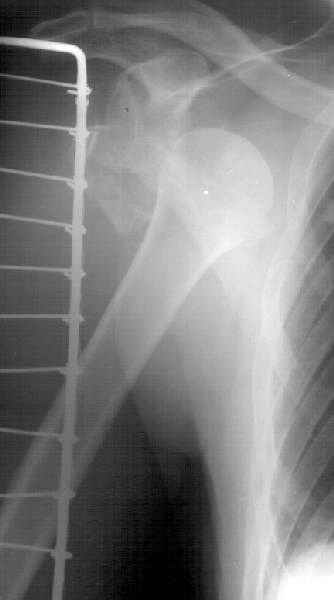

Мужчина 61 г., получил 6.04.02 в ДТП (лобовое столкновение) вывих плеча с переломом большого бугорка и не бросающимся в глаза переломоманатомической шейки (см здесь ). В ЦРБ под в/в наркозом дежурный врач (ЛОР по специальности) попытался вправить плечо. Контрольный снимок

сделан через день (фас, аксиальная). Из сопутствующей патологии - болезнь Рейно, 2 года назад какая-то сосудистая операция (выписки нет, 15 см рубец под мышкой), от которой положительного эффекта не отметил.Есть холодность и мраморность предплечья и кисти, стойкие контрактуры пальцев. Эндопротезирование плечевого сустава в число доступных методик не входит. Намереваемся сделать открытую репозицию и фиксировать пластинкой, если будет нестабильность, то и спицами трансартикулярно. Очевидно, что есть высокий риск аваскулярного некроза головки, о чем пациент предупрежден. Есть ли альтернативы такому плану? Может быть, какая-то подвешивающая операция тут предпочтительнее, или дополнить остеосинтез подвешиванием плеча к акромиону? Или вообще не оперировать, а пойти на раннюю функцию по стихании болевого синдрома? Заранее спасибо. -- Best regards, Alexander N. Chelnokov